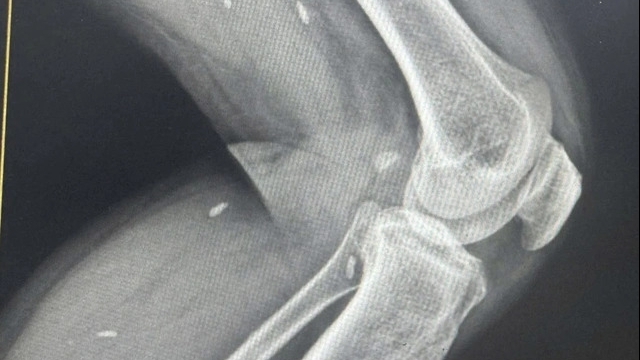

Kết quả chụp cắt lớp vi tính ghi nhận, chị H bị chấn thương gan độ III-IV, có ổ thoát mạch, tụ máu quanh gan và vùng hạ vị; gãy xương sườn 4,5 bên phải, tràn dịch màng phổi phải.

Bệnh nhân trong tình trạng sốc, rối loạn đông máu nên lựa chọn tối ưu là chụp và nút mạch số hóa xóa nền, kết quả ghi nhận ổ thoát mạch từ nhánh động mạch gan phải.

BSCKII Trần Công Khánh – Phó khoa Chẩn đoán hình ảnh đã thực hiện bơm tắc bằng hỗn hợp keo. Chụp kiểm tra sau bơm tắc không thấy thoát mạch.